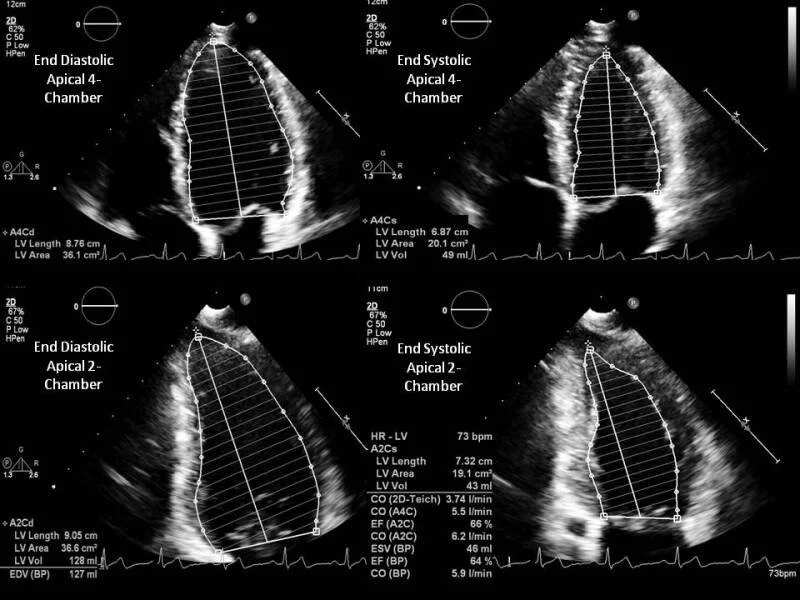

Simpson Biplane:

This is the gold-standard for measuring LV volumes and EF with echo (named after the mathematician Thomas Simpson, but current nomenclature is to avoid possessive eponyms). It requires an algorithm programmed into the ultrasound machine, but most POCUS machines will have this capability.

Biplane measurements require two apical views to be obtained (the two “planes“):

• Apical 4-chamber, and at 90 degrees to this the

• Apical 2-chamber

In both of these views, the endocardial border is carefully traced at end-systole, and end-diastole, to calculate the LV areas in the two views. The biplane measurement then converts these measurements into a series of twenty disks to calculate the volume.

See the image below to get an idea of how a bi-plane measurement works.

An example of how to calculate LVEF using the biplane method, tracing the endocardial border in both the A4C and A2C views in a normal heart.